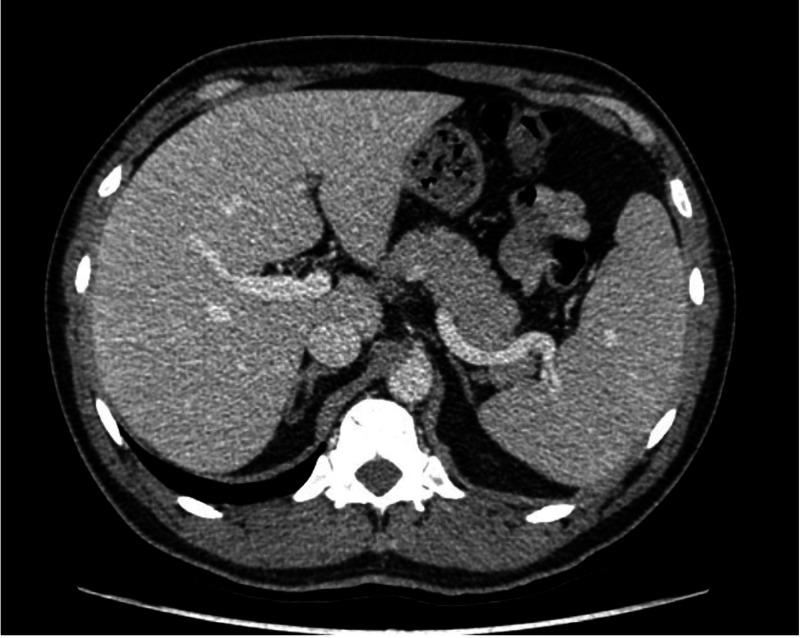

一名既往诊断为恶性贫血的患者在补充钴胺素后发生自身免疫性溶血性贫血:病例报告

Autoimmune Hemolytic Anemia After Cyanocobalamin Replacement in a Patient With a Previous Diagnosis of Pernicious Anemia: A Case Report.

Pernicious anemia (PA) is associated with other autoimmune diseases, such as hypothyroidism, type 1 diabetes mellitus (DM1), Addison's disease, and vitiligo. The association between PA and autoimmune hemolytic anemia (AIHA) is rare, with less than 30 cases reported in the literature. In this paper, we report a case of a patient with a confirmed diagnosis of PA, who, six months after starting treatment with cyanocobalamin, presented with severe hemolysis with a positive direct antiglobulin test (DAT) for warm antibodies; the patient responded well to glucocorticoid treatment. AIHA in PA patients can be triggered by cyanocobalamin replacement due to the expression of membrane antigens by mature red blood cells entering into the peripheral circulation. This association should be considered because these patients, in addition to cyanocobalamin replacement, will require immunosuppressive treatment, usually with glucocorticoids.

摘要

恶性贫血(PA)与其他自身免疫性疾病相关,如甲状腺功能减退、1型糖尿病(DM1)、艾迪生病和白癜风。PA与自身免疫性溶血性贫血(AIHA)之间的关联较为罕见,文献报道的病例不足30例。在本文中,我们报告了一例确诊为PA的患者,该患者在开始使用氰钴胺治疗六个月后,出现严重溶血,直接抗球蛋白试验(DAT)显示温抗体阳性;患者对糖皮质激素治疗反应良好。PA患者发生AIHA可能是由于进入外周循环的成熟红细胞表达膜抗原,从而引发氰钴胺替代治疗。应考虑到这种关联,因为这些患者除了进行氰钴胺替代治疗外,通常还需要免疫抑制治疗,一般使用糖皮质激素。